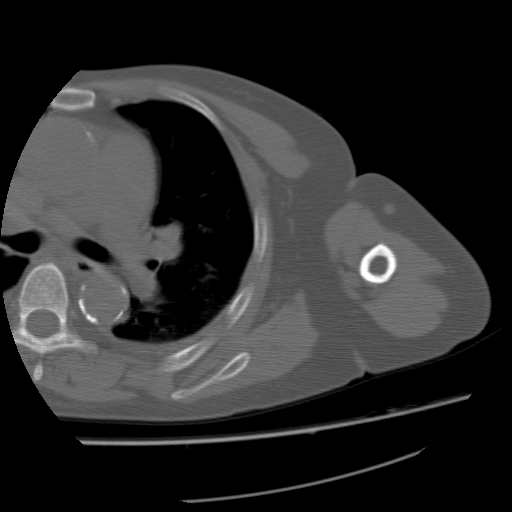

CT52706:女,45岁,慢性肾功能衰竭约5年

女,45岁,慢性肾功能衰竭约5年,左肩关节肿痛一年余

左侧肩峰及肱骨头周围可见大量钙化。结合临床病史考虑:肾性骨关节病可能性大。

加扫右侧肩关节见相似钙化,符合肾性骨关节病表现

肾性骨 关节病。